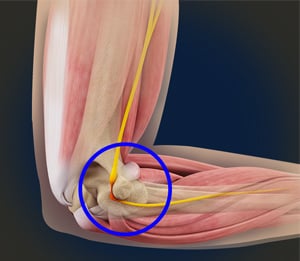

The ulnar collateral ligament (UCL) is a connective tissue that connects the humerus (upper arm bone) to the ulna (lower arm bone). When the UCL is fully or partially torn, the elbow does not have the ability to withstand significant amounts of valgus stress, causing pain and instability in the medial (inside) elbow.

- Ulnar nerve transposition – The ulnar nerve naturally resides on the back side of the elbow, but often, surgeons will move the nerve to the front of the elbow in order to avoid it being stretched or irritated. Not all patients will require this, and it’s typically based on the doctor’s discretion. A nerve that is stretched, inflamed, or compressed can significantly delay the rehab process.